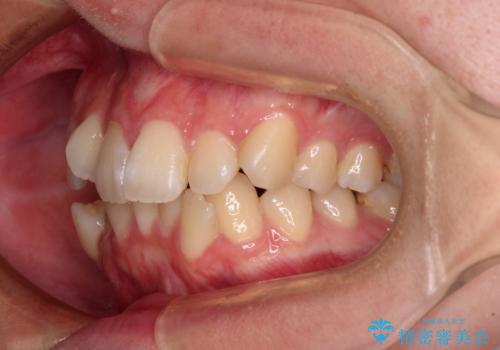

- 上下前歯のデコボコを気にして来院された患者様です。

口元の突出感はあまりなかったものの、デコボコを非抜歯で改善すると出っ歯になる可能性があるため、上下左右の第一小臼歯4本を抜歯し、ワイヤー装置にて矯正治療を行うこととしました。

口元の突出感はなかったものの、捻転や八重歯を改善するために補助装置を併用する必要がありました。

予定の2年半を越えてしまいましたが、無事にきれいな口元に仕上げることができました。